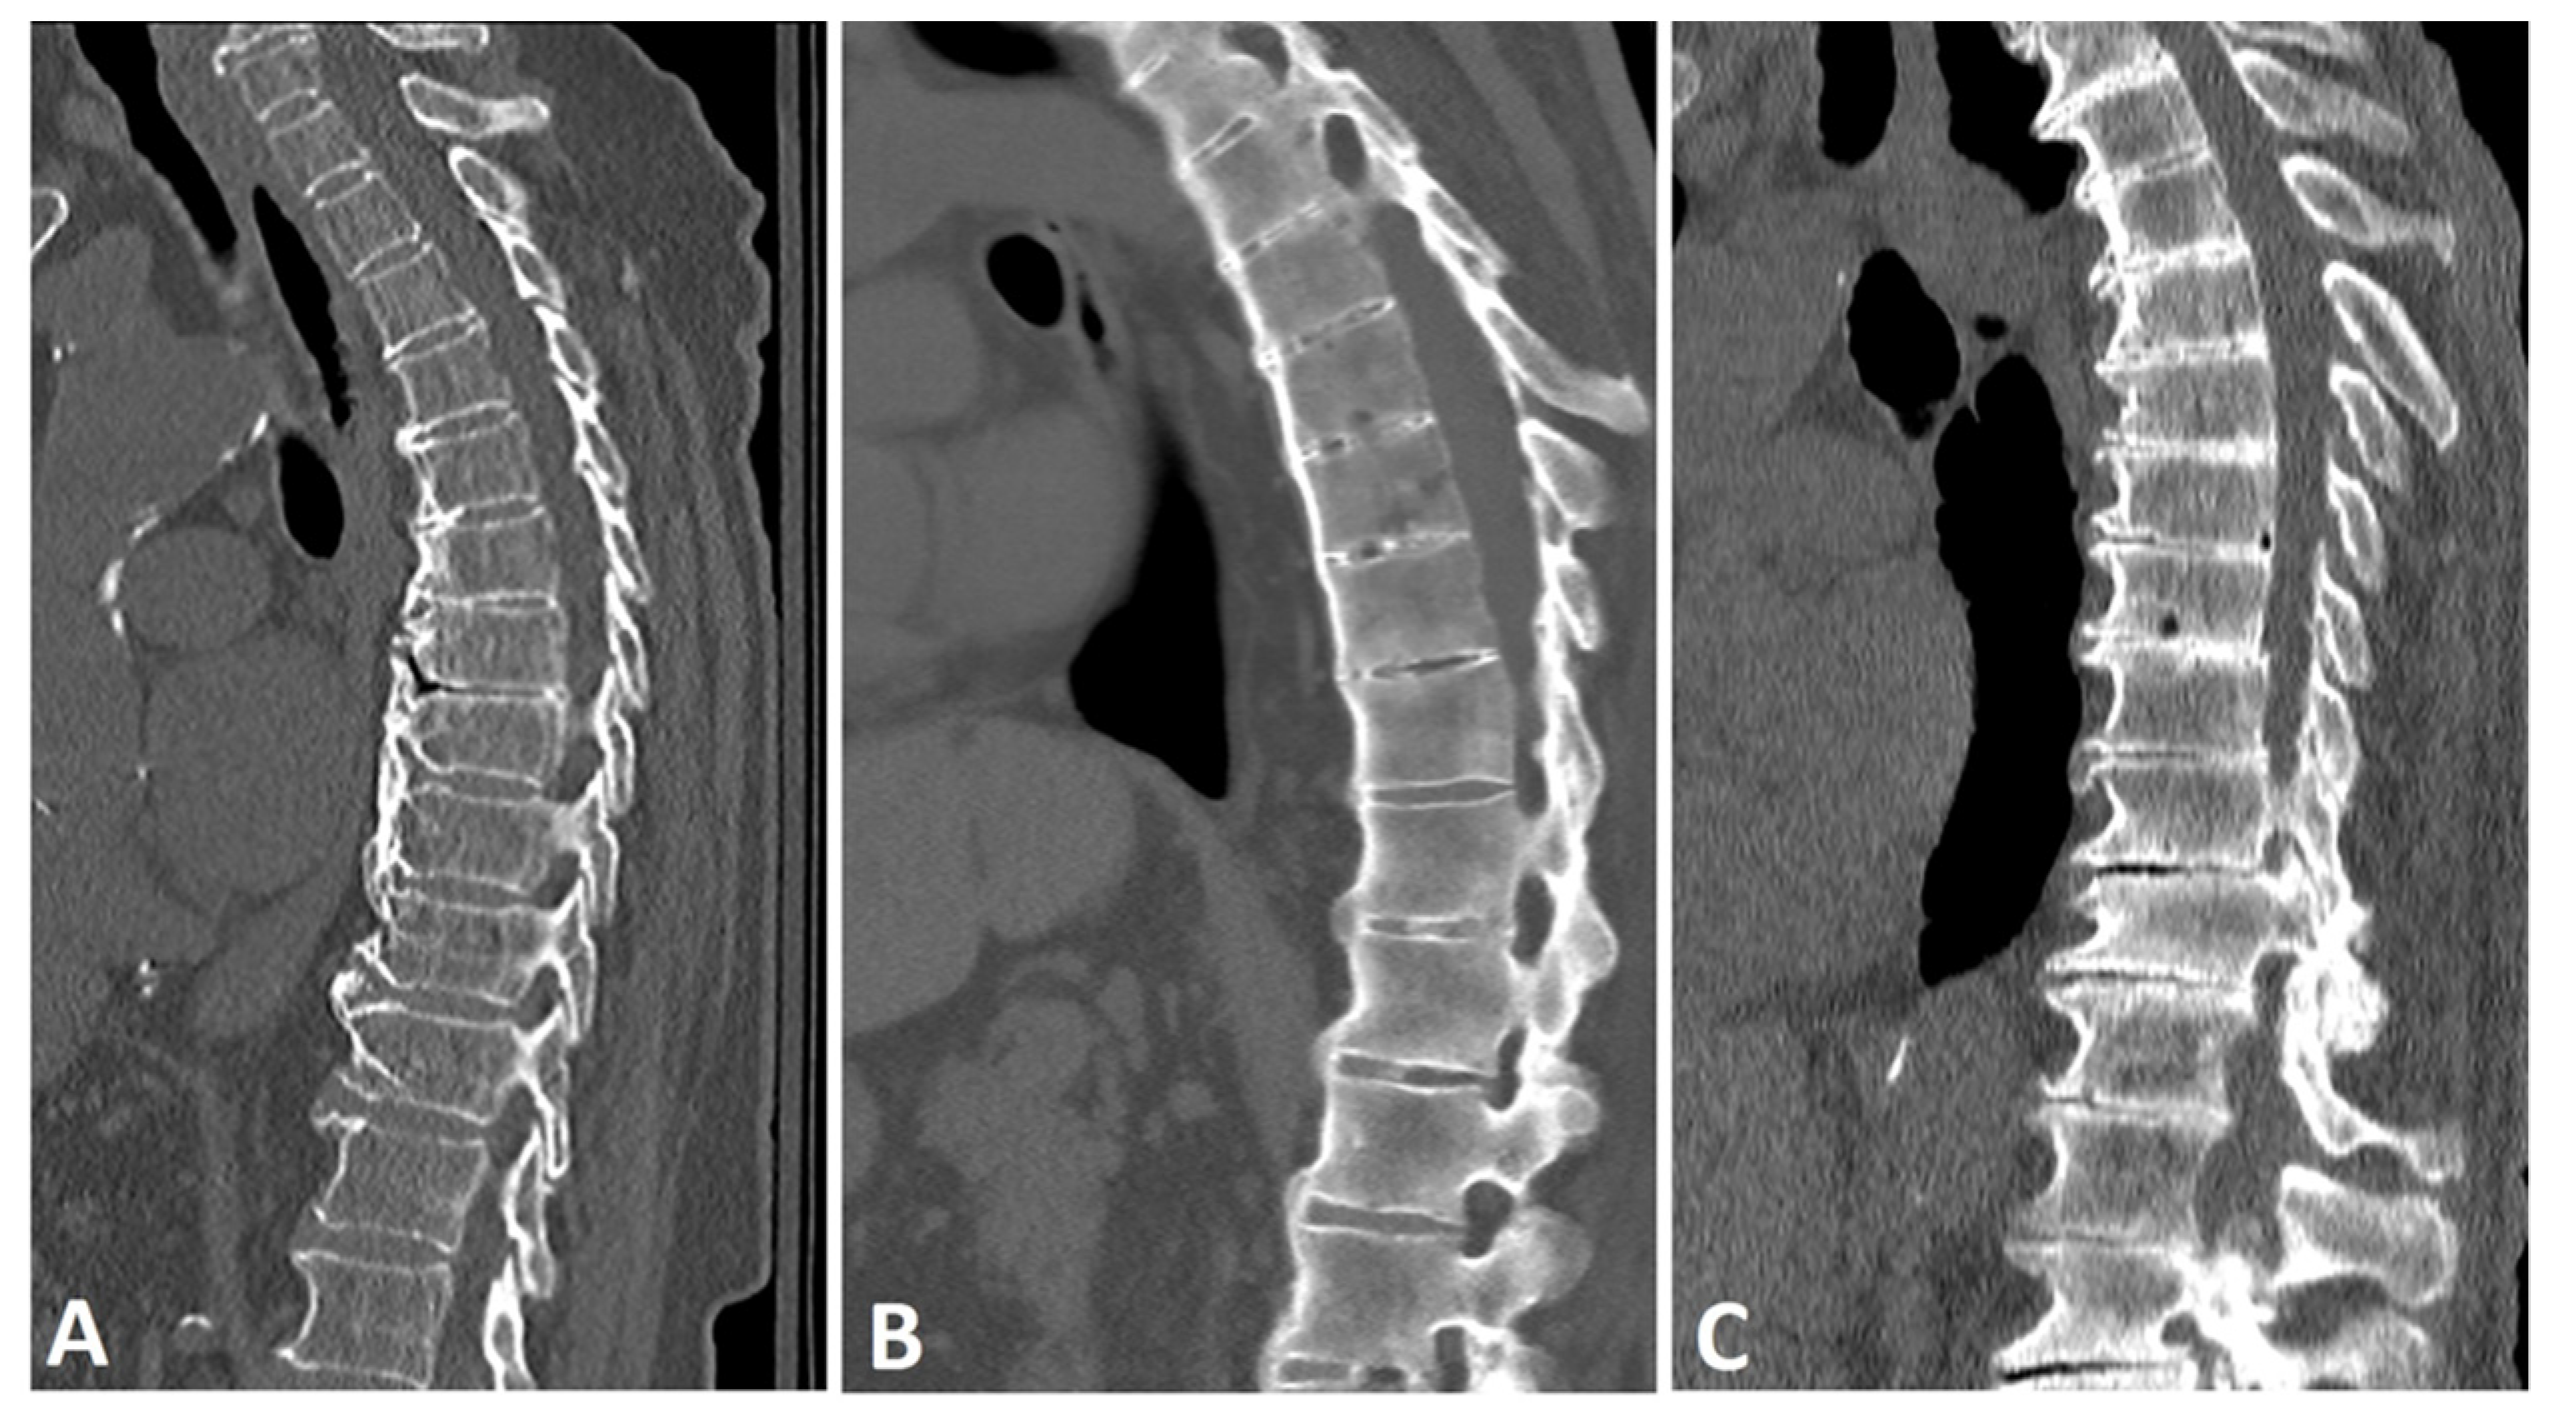

Figure 1.

Sagittal CT reconstructions of the thoracic spine in three different patients: (A) a patient with DISH with thick, flowing, horizontally oriented, coarse osteophytes; (B) a patient with AS with slender, vertically oriented syndesmophytes; and (C) a patient with degenerative disc disease with horizontally oriented, non-flowing osteophytes. Note that the disc space is relatively preserved in the DISH subject, but not in the patient with a degenerative spine.